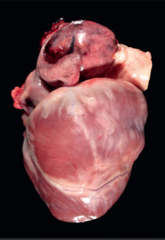

acute, severe, ecchymotic, Endocardial Hemorrhage

Front

morphological diagnosis

heart: right atrium, hemangiosarcoma